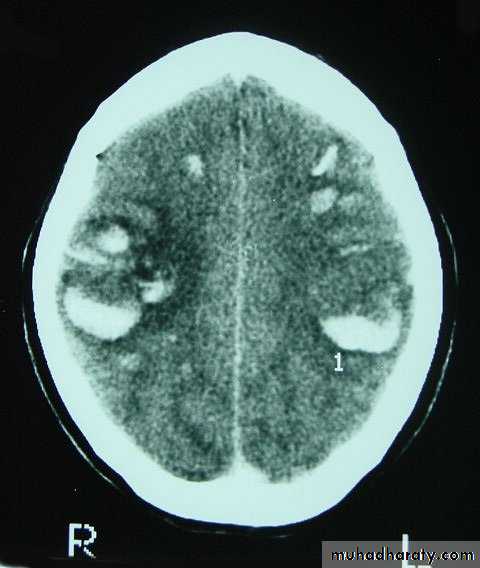

3. Brainstem and hemispheric (Cerebral) Contusion

These are areas of bruising and swellings with intact pia arachnoid, localized or generalized oedema and haemorrhage due to tearing of blood vessels.

3. Cerebral Contusion

Clinical presentations:

1. Prolonged periods of unconsciousness.

2. Focal neurological deficits that persist for longer than 24 hours.

CT scans demonstrates contusions as small areas of haemorrhage in the cerebral parenchyma.

Contusions may resolve with the accompanying deficits or they may persist.